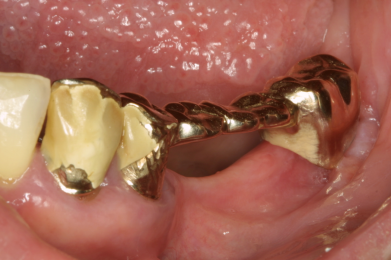

- Defekte oder braune, schwarze Stellen an den Zähnen, Kronen oder Brücken / Verweigerung von Essen wegen Heiß-/Kaltempfindlichkeit oder Empfindlichkeit süß-sauer / „Fährt rein!“

- Scharfe Kanten an den Zähnen / Verletzungen an Zunge oder Schleimhäuten fallen auf oder werden beklagt / Ständiges Spielen der Zunge an den Zähnen

- Es fällt auf, dass ein oder mehrere Zähne stark wackeln oder eine Brücke lose ist

- Eine Krone oder Brücke ist aus dem Mund gefallen